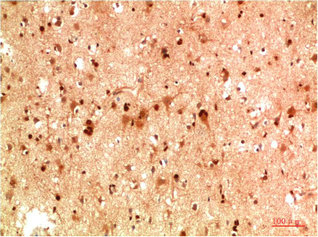

Western blot analysis of 1) C2C12 Cell Lysate, 2)PC12 Cell Lysate, 3) Hela Cell Lysate using HSP40 Rabbit pAb diluted at 1:1000.